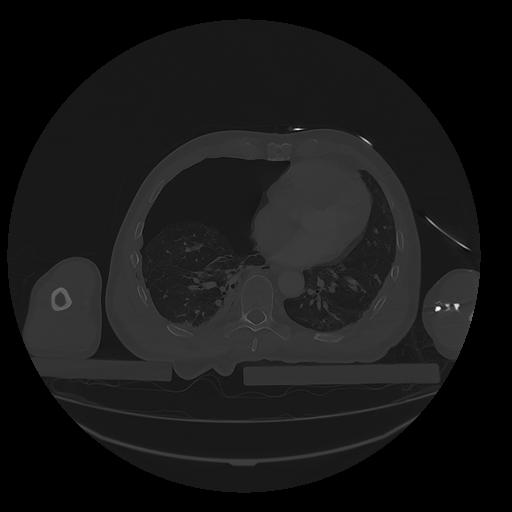

31 PULMON,CE,Vol,1.0,PULMON,,